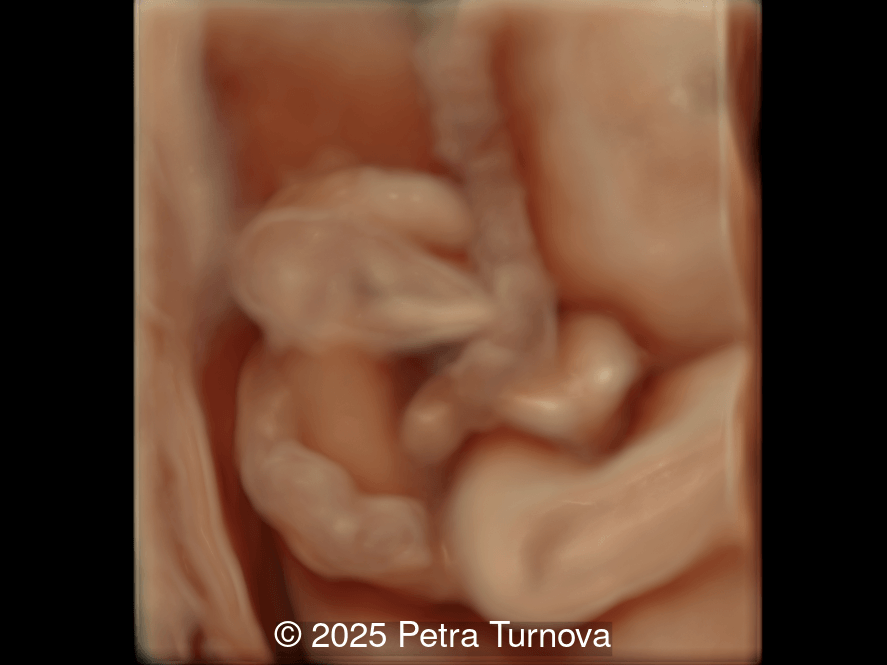

Our imaging revealed malformations in all four limbs with elbow, wrist, and knee joints fixed in extension, as well as foot and ankle malformations. Profile abnormalities were observed with prefrontal edema, flat profile and retro-micrognathia. Ultrasound demonstrated minimal stomach filling related to a lack of swallowing ability and hypoplastic lungs due to poor diaphragmatic movement. Nuchal edema was present.